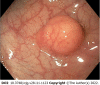

Rectal neuroendocrine neoplasms (r-NENs) are considered among the most frequent digestive NENs, together with small bowel NENs. Their incidence has increased over the past few years, and this is probably due to the widespread use of endoscopic screening for colorectal cancer and the advanced endoscopic procedures available nowadays. According to the current European Neuroendocrine Tumor Society (ENETS) guidelines, well-differentiated r-NENs smaller than 10 mm should be endoscopically removed in view of their low risk of local and distant invasion. R-NENs larger than 20 mm are candidates for surgical resection because of their high risk of distant spreading and the involvement of the muscularis propria. There is an area of uncertainty regarding tumors between 10 and 20 mm, in which the metastatic risk is intermediate and the endoscopic treatment can be challenging. Once removed, the indications for surveillance are scarce and poorly codified by international guidelines, therefore in this paper, a possible algorithm is proposed.